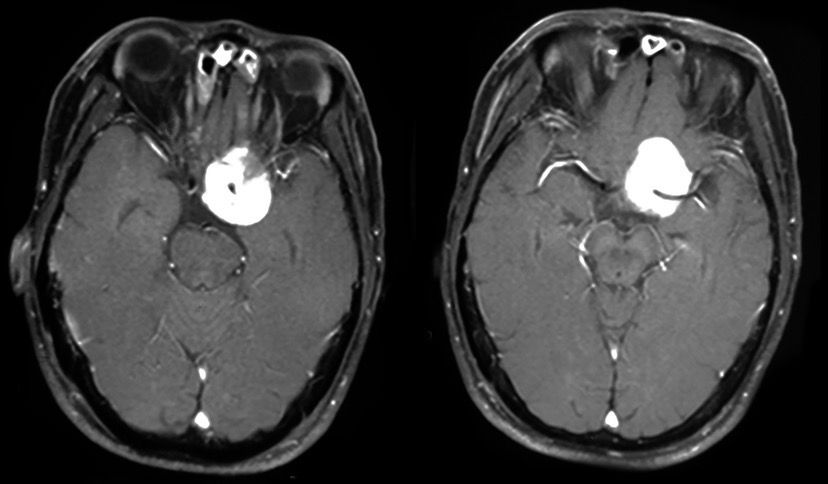

术后MRI检查提示肿瘤全切。

术后随访:无新发神经功能障碍,左眼视力较术前好转(L 0.6/R 0.8)。

术后MRI复查: